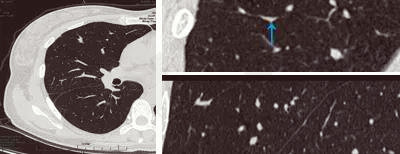

無獨有偶,34歲的張女士在一次體檢中發(fā)現肺部有肺磨玻璃影,在結節(jié)的性質沒有確定前,她焦慮萬分,“我沒有咳嗽又沒有發(fā)燒怎么會有肺結節(jié)呢?”“肺磨玻璃結節(jié)是不是就是肺癌?”“要手術嗎?” ……帶著一連串疑問,她來到肺結節(jié)影像??崎T診就診,經影像??漆t(yī)生的檢查識別,明確診斷為斜裂局部胸膜增厚所致假病灶,從而徹底解除了張女士的擔憂。

局部胸膜增厚